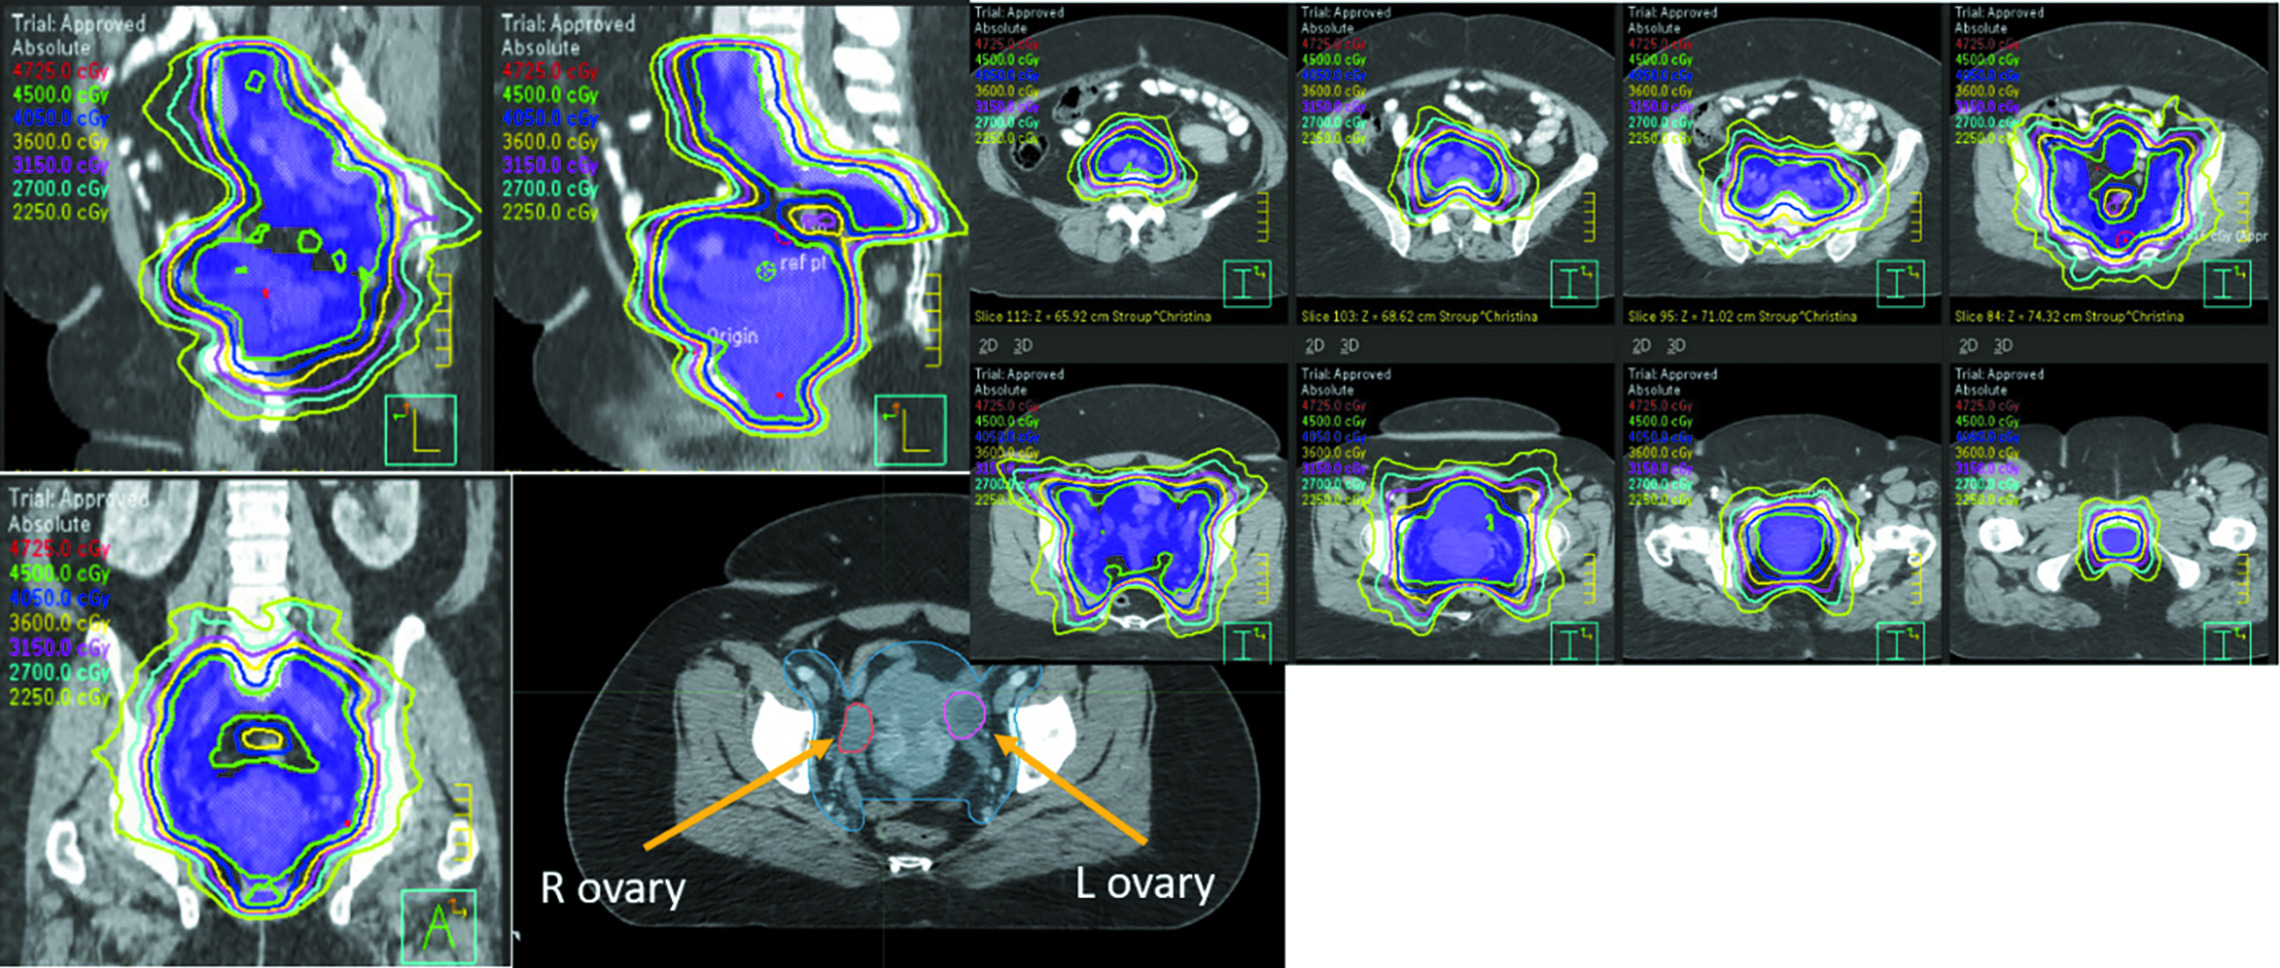

The late side effect that most commonly comes to mind when thinking about AYA patients is loss of fertility. Approximately 50% of cervical cancer patients are premenopausal at diagnosis and 15% of rectal cancer patients are under the age of 50 at diagnosis.4 Even low doses of pelvic RT can cause a total shutdown of ovarian function in women of this age group, with doses of less than 4 Gy (and even less than 2 Gy) associated with the elimination of 50% of the oocyte pool.5 Standard pelvic dosing of 45-50 Gy (Figure 1) also leads to uterine vascular changes that make future successful gestation of a pregnancy unlikely. When counseling patients, it is important to discuss loss of fertility and premature ovarian insufficiency (POI), also known as premature menopause, at the initial consultation. This includes discussion surrounding ovarian shutdown leading to loss of viable eggs and inability to carry a full-term pregnancy due to uterine changes after radiation.

Another option for patients who do not have ovarian involvement by tumor is surgical ovarian transposition.10 With this procedure, the ovary is surgically transposed with its vascular pedicle to another location, ideally well above the pelvic brim, to minimize the radiation dose to the ovary. The procedure is most often performed laparoscopically, allowing for relatively quick recovery times. Transposition can be performed concurrently with other surgical procedures (such as pelvic node debulking, para-aortic nodal sampling, diverting ostomies, or hysterectomy/trachelectomy) or as stand-alone surgery. The ovaries should ideally be transposed at least 3 cm above the upper border of the radiation field, well above the pelvic brim and as lateral as possible (Figure 2). Although the data for ovarian transposition are somewhat limited, a 2021 Italian review of 28 manuscripts (including 699 patients with cervical cancer undergoing ovarian transposition and RT ± chemotherapy) showed that transposition was able to preserve ovarian function in 62% of patients. Ovarian preservation in these studies was defined as FSH < 10 mIU/mL, E2 > 50 pg/mL, and the presence of follicles on ultrasound. The type of treatment had implications on ovarian preservation rates as well, with an 86% preservation rate with brachytherapy alone vs a 55% preservation rate in patients who received external-beam radiation therapy + brachytherapy.11 Complication rates are typically low, with a reported rate of approximately 8.5%.12 Laparoscopic ovarian transposition is recommended due to decreased complication rates, reduced time to starting pelvic RT, and very high ovarian survival rates.13,14 Studies have shown that in women under age 40 who underwent laparoscopic ovarian transposition, ovarian function preservation rates were as high as 88.6%.15 There are no consensus guidelines on dose constraints to transposed ovaries, and ideally, the dose to the transposed ovary or ovaries should be as low as possible. However, one study looking at women treated with intensity-modulated radiation therapy after ovarian transposition showed that dose constraints of a maximum dose < 9.985 Gy, mean dose < 5.32 Gy, and V5.5 < 29.65% to the transposed ovary could be better at preventing ovarian dysfunction, especially in women under age 38.16

CT simulation can typically be performed within a week of the procedure if the abdominal wall has sufficiently deflated (after surgical insufflation with laparoscopy) for reproducible treatment planning and delivery. The surgeon should mark the location of the transposed ovary or ovaries with a surgical clip and the ovarian tissue should be contoured for dosimetric evaluation. If the ovary is high enough in the abdomen, there should be minimal direct dosing to the ovary; however, the ovary will likely still receive some radiation exposure via internal scatter. This is important to explain when counseling patients, as the risk of ovarian failure remains given the tissue’s sensitivity to radiation. Other risks associated with ovarian transposition include complications at the time of surgery, ovarian torsion, vascular injury, fallopian tube infarction, and small bowel obstruction due to postsurgical adhesions. Ovarian cyst formation is common and reported in up to 95% of patients but is unlikely related to the transposition procedure. Patients who undergo successful ovarian transposition with function retained after radiation therapy may retain viable eggs after treatment, which can later be retrieved for in vitro fertilization procedures. Ovarian transposition tends to be more successful in younger women, with the best outcomes seen in patients under age 35 (preservation rates by age: 25-30: 87.5%; 31-35: 62.5%; and 35-40: 42.9%).17 National guidelines by the American Society of Clinical Oncology and the National Cancer Comprehensive Network3,18 both recommend offering ovarian transposition to appropriately selected AYA cancer patients (Table 2) and referral to psychosocial providers when patients are distressed about potential infertility.